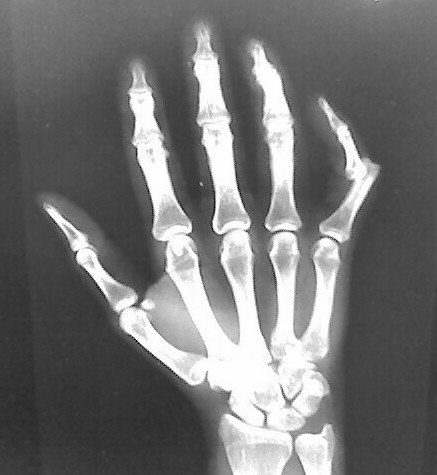

Your doctor will suspect that your finger is dislocated if it appears swollen and deformed.

In some cases, your doctor may order an X-ray of your finger if he or she suspects that there is also fractures together with the dislocation. What happens when there is a combination of BOTH fracture and dislocation, the finger bone can end up being pulled away from connected tendons.

This is a is common occurrence for a fragment of bone to separate from the main bone and stay with the tendon, a condition known as an avulsion fracture.